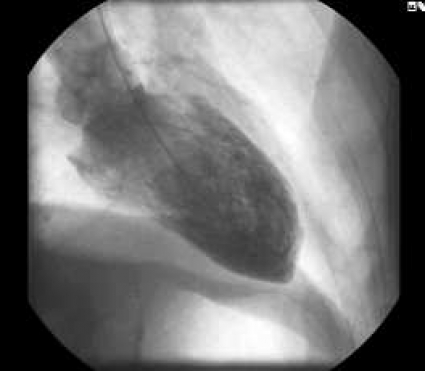

Fall 1 rör en 78-årig man, rökare med avancerad kroniskt obstruktiv lungsjukdom, som med hjälp av hemtjänsten inkom på grund av tilltagande andfåddhet. Vid ankomsten noterades en syrgassaturation på 67 procent. Patienten förbättrades efter inhalationsbehandling och steroider. EKG visade påtagliga ST-höjningar (Figur 2) och bedömdes som pågående akut hjärtinfarkt trots avsaknad av centrala bröstsmärtor. Akut koronarangiografi visade väsentligen normala kranskärl. Angiografi av vänster kammare visade dock betydande nedsättning av vänsterkammarfunktionen med akinesi/dyskinesi antero- och inferoapikalt samt hyperkinesi inom basala segment (Figur 3 A–B). Därutöver sågs ett betydande läckage i mitralisklaffen.

Efter undersökningen var patienten relativt välmående. Man fortsatte med andningsvård, inhalationer och startade behandling med ACE-hämmare i låg dos. Plasmavärdet av troponin I nådde som mest 3,0 (my)g/l (referensvärde 0,1 (my)g/l), medan CK-MB nådde 22 mg/l (referensvärde 4,0 (my)g/l). Dag 2 förflyttades patienten till hemortslasarettet och kunde så småningom skrivas ut.

Angiografisk kontroll ca 3 månader senare visade normaliserad vänsterkammarfunktion (Figur 3 C–D) med regress av både den apikala dyskinesin och mitralklaffläckaget. EKG i samband med kontrollangiografin visade regress av ST-höjningarna, normalisering av R-vågsprogressionen och tillkomst av T-vågsinversion (Figur 2).